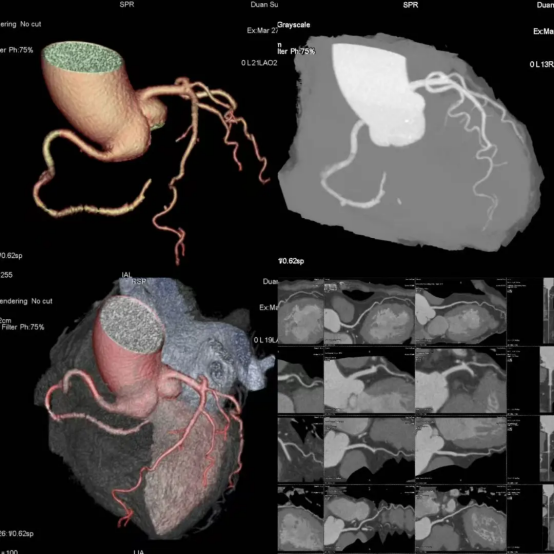

0.625mm超薄层厚扫描,连微小斑块、钙化都无处遁形,清晰度提升30%+!

360°三维立体成像,血管走行、狭窄程度一目了然,诊断更精准。